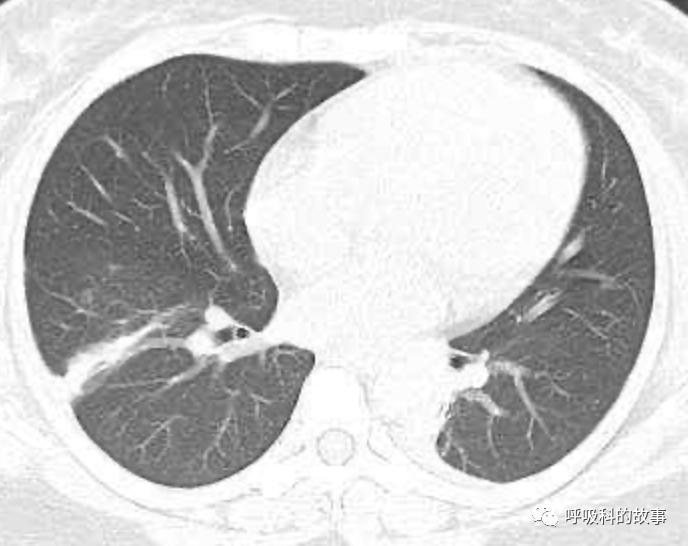

患者发热后行胸部CT检查(6月21日,住院第13天),可见两下肺有条片影,当时考虑是肺炎引起的发热。

可是在6月26日(往院第18天)仍持续发热的情况下复查肺部CT,肺部病灶已明显吸收了。那么患者发热的原因到底是什么呢?为什么患者高热的情况下血白细胞不升反降,C反应蛋白也没有明显增高?这个时候消化科医生也迷茫了,这可怎么办?于是请感染科和呼吸科医生一起会诊,共商计策。